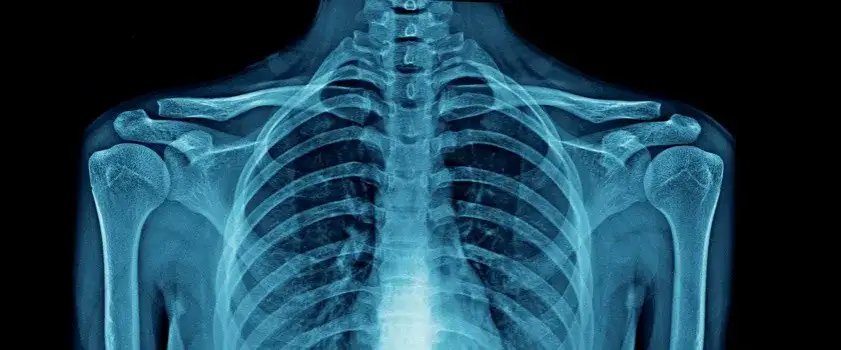

- Diagnostyka opiera się na badaniach obrazowych, takich jak RTG.

Diagnostyka sklerotyzacji stropu panewki opiera się głównie na badaniach obrazowych. Techniki takie jak RTG są niezwykle istotne, ponieważ mogą ujawniać charakterystyczne zmiany sklerotyczne oraz inne objawy degeneracyjne. Wczesne rozpoznanie może znacząco wpłynąć na wybór odpowiedniego leczenia.

RTG | Obrazowanie stawów w celu identyfikacji zmian sklerotycznych. |

Rezonans magnetyczny | Dokładniejsze badanie tkanek miękkich i chrząstki. |

Tomografia komputerowa | Pomaga w ocenie stanu kości i tkanek w stawie. |